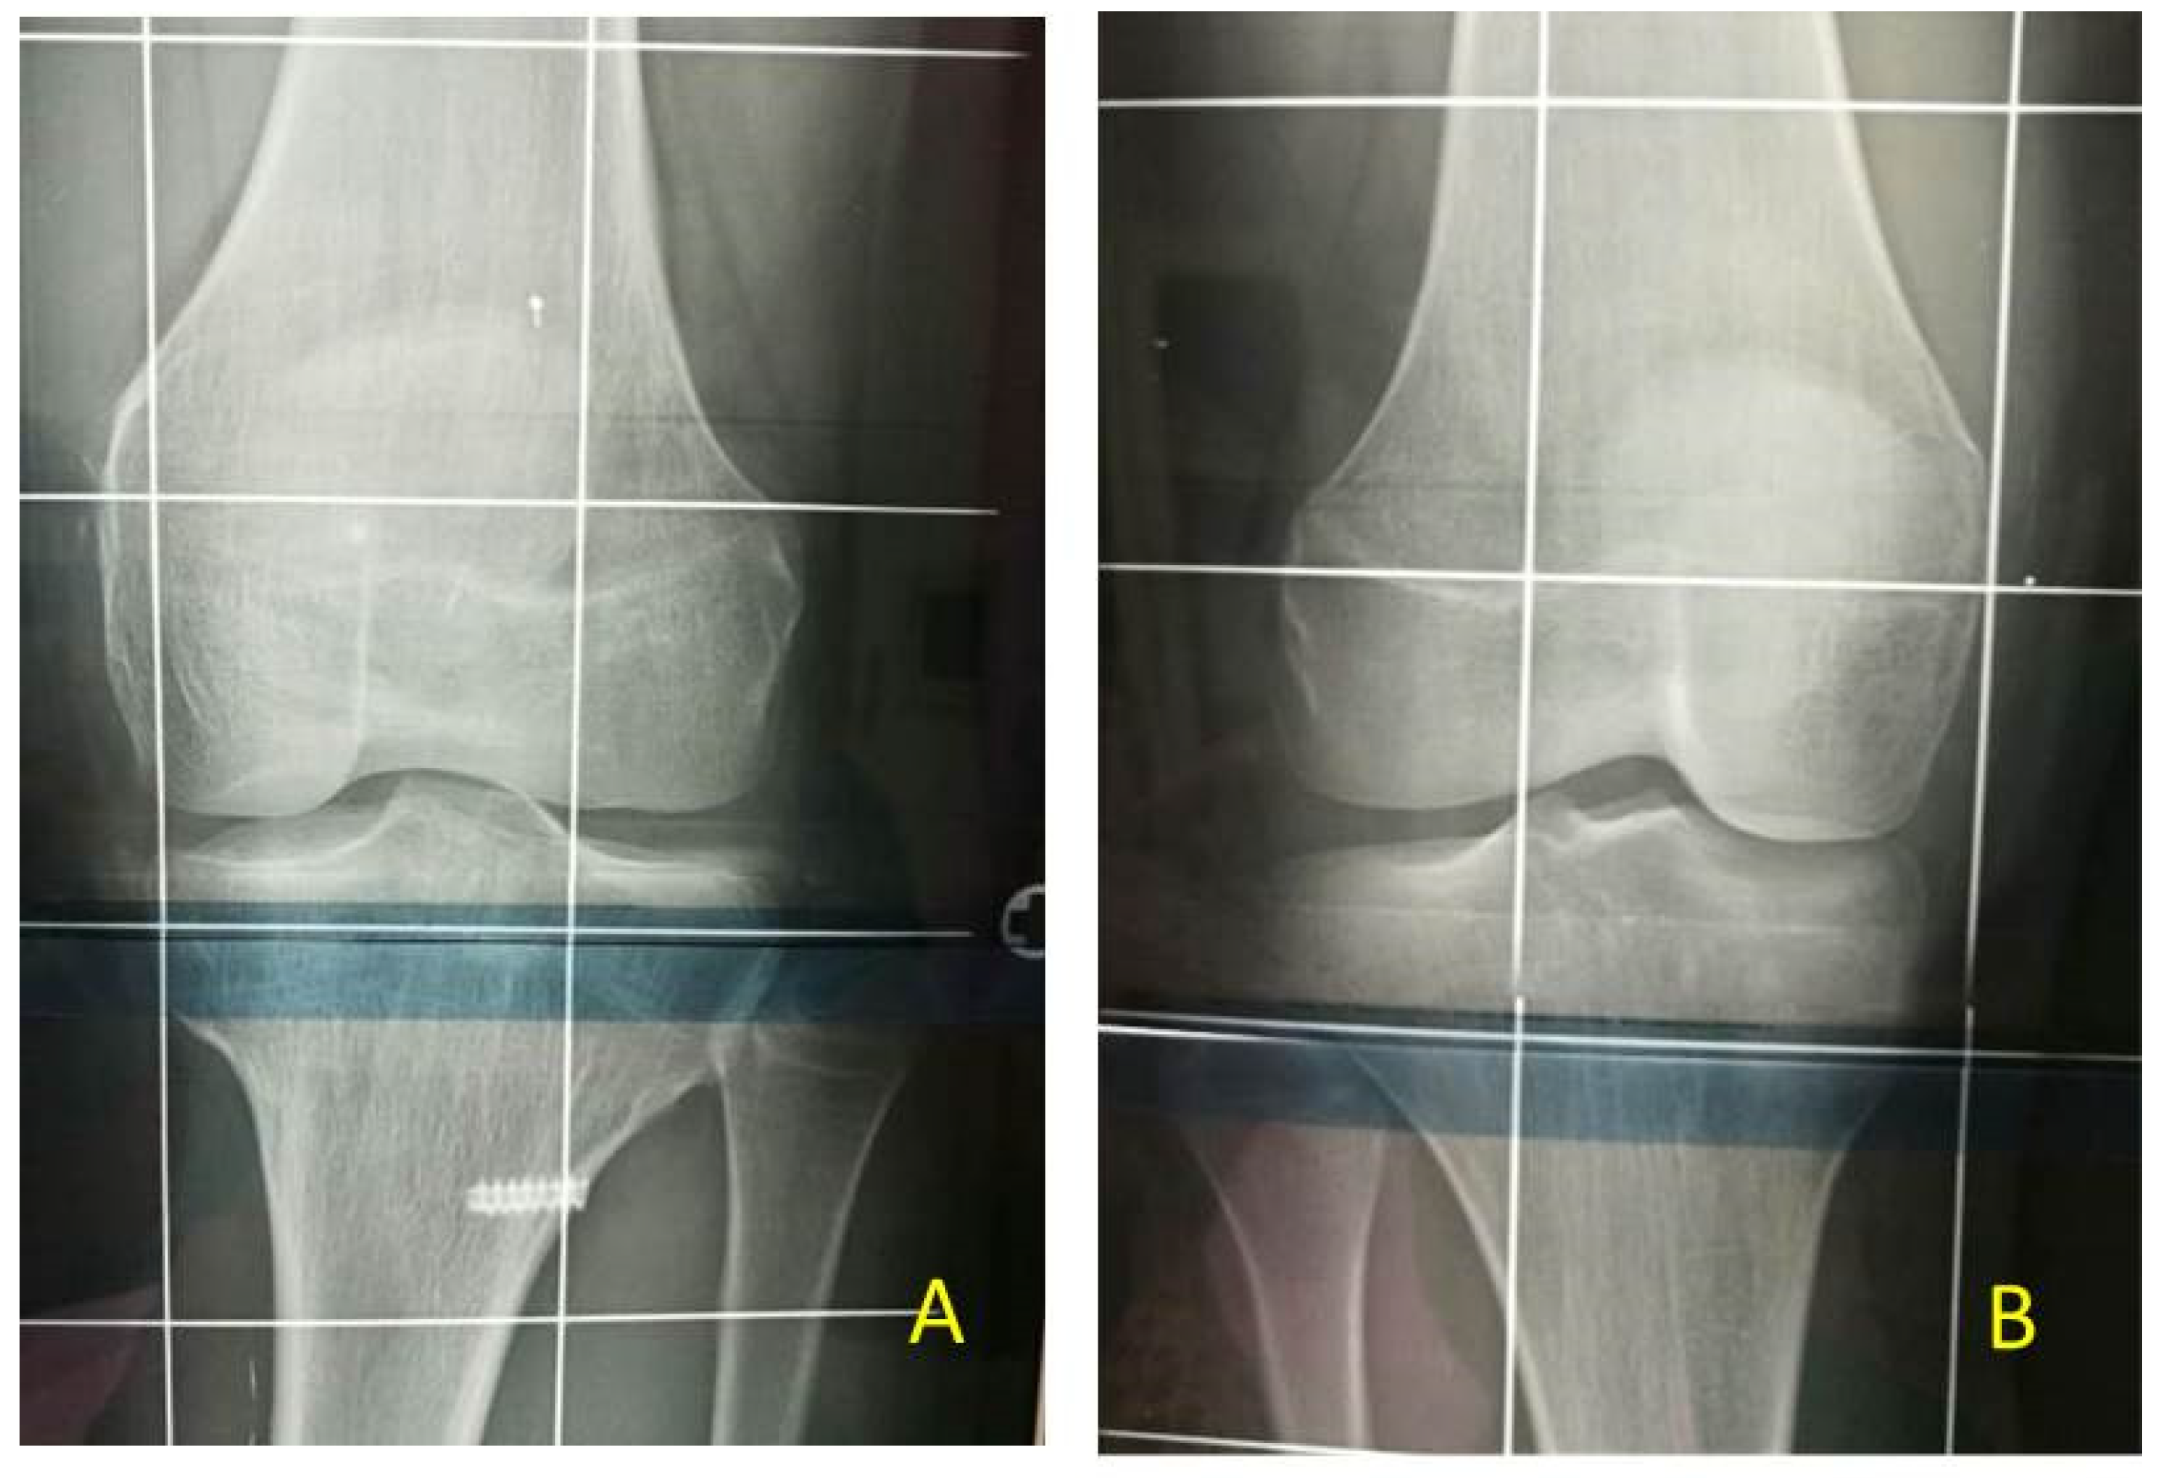

The most relevant orthopedic feature is LO, which can cause leg length discrepancy (LLD) involving both the femur and tibia (Figure 1). In literature, only 43–65% of patients are reported to have LLD [4].

Figure 1. BWS (Beckwith-Wiedemann syndrome) patients at different ages with LO (lateralized overgrowth) and LLD (leg length discrepancy) involving both femur and tibia: (A) nine-month-old neonate with LO and mild (<2 cm) LLD right; (B) three years old male child with critical (>5 cm) LLD right; (C) eight-year-old female child with severe (2–5 cm) LLD left.